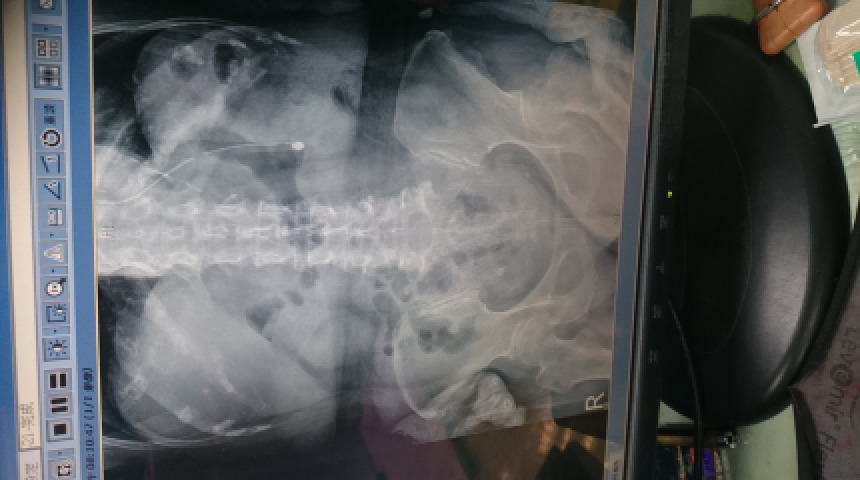

老媽咳嗽不明熱的經驗分享 抗生素針劑的使用 尿管抽換 噴霧器清理 鼻胃管的長度 中醫食物的禁忌

老媽住院與出院後CPR發炎延緩指數的認識 低血鈉的檢討與處置 24穀粉必須持續添加鹽才能符合鈉的需求 體重持續穩定增加